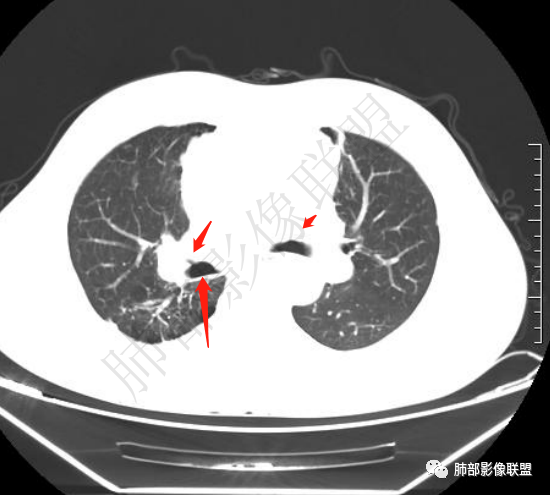

▲右上叶、下叶胸膜下为主的斑片实变影,局部结构变形。支气管后移。支持慢性炎性病变,结核可能。从这个角度分析:纵隔肿瘤与肺部病灶关系不密切。

3.右肺上叶体积缩小并见边界较为清楚的条片影及结节影,密度较高且不均,期间显示支气管扩张。

4.右肺门及纵隔见钙化淋巴结。

2.右肺上叶病灶,纤维硬结灶及支扩等,应该存在时间较长。